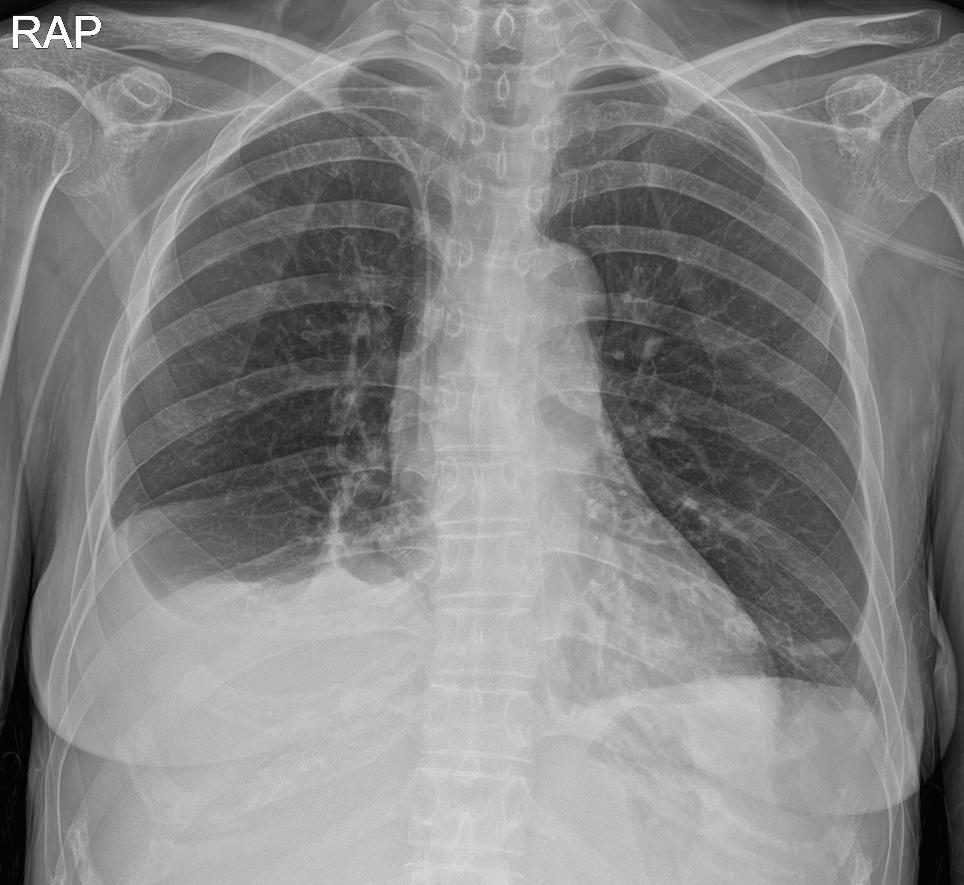

아직 많이 보편화되어있지는 않지만 저희 병원에서 흉부 X-ray 판독의 경우 AI 판독이 한번 더 시행됩니다.

X-ray를 찍게되면 저희가 보고, 영상의학과 전문의가 판독을 달고, AI 판독이 또 나오고 이렇게 AI 만 사용하지는 않고 여러번 검증하는 차원에서 도움을 받고있습니다.

아래 사진에서 보시면 밑에 사진이 AI가 어떤 문제가 있을것 같다 하고 정보를 제공해준겁니다.

지금은 흉부 X-ray 뿐이지만 이게 점점 더 넓은 영역으로 넓어질거라고 생각합니다.

하지만 AI 판독만을 완전히 믿을수는 없고 저희가 한번 더 확인을 하는 절차가 필요할 거라고 생각됩니다.